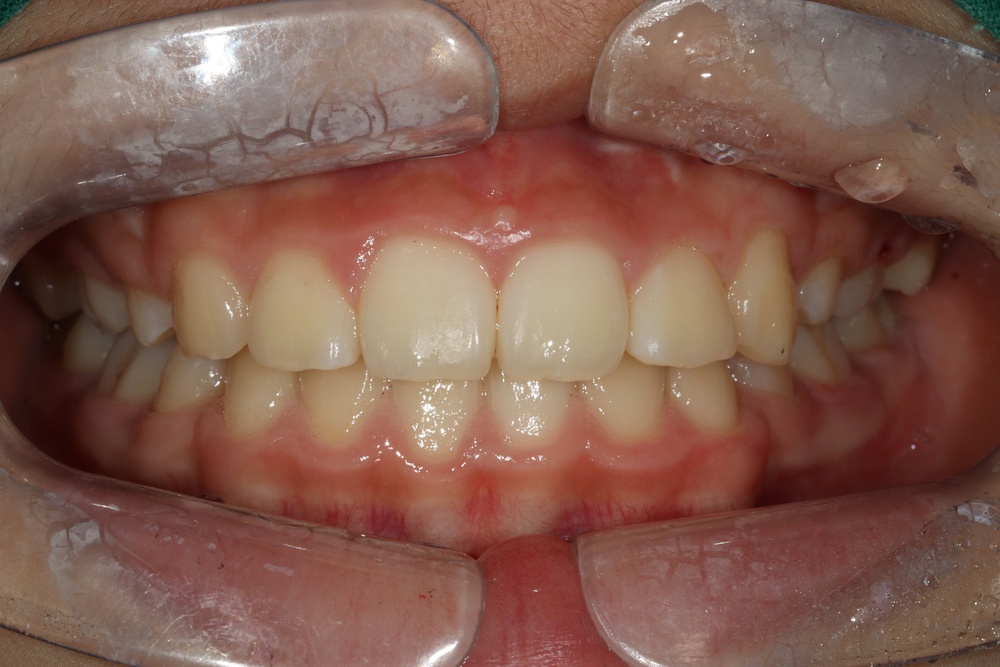

40대의 환자분으로, 앞니가 비뚤어서 코로나가 끝났을 때 마스크를 벗고 웃고 싶다고 하셨습니다.

충치가 많아서 교정 전 충치치료를 전반적으로 시행하고, 잇몸치료도 진행하였습니다.

중년기 교정에서 발생가능한 문제점(치아 사이 틈 발생가능성, 잇몸질환)충분히 설명드리고 시작하였습니다.

치아 배열이 거의 완성된 상태로 치료 전 말씀드렸던 치아사이의 틈(블랙트라이앵글)이 있습니다.

환자분과 상의 후 위쪽은 벌어진 공간을 레진으로 메꾸기로 하였습니다.

치아가 가지런해졌고, 윗니 치아 사이의 틈도 메꿔졌으며, 치아에 있던 충치도 모두 치료하였습니다.